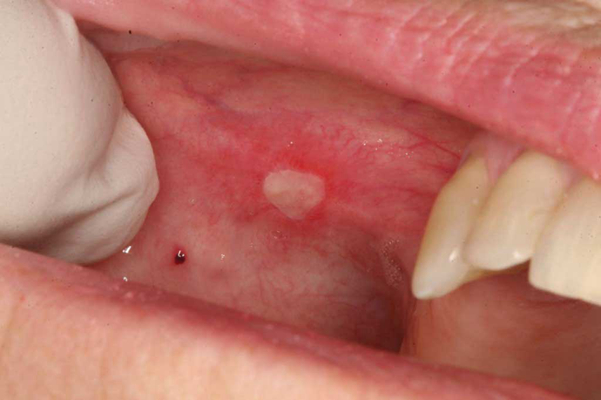

口腔癌圖片

口腔癌的前兆 (9)